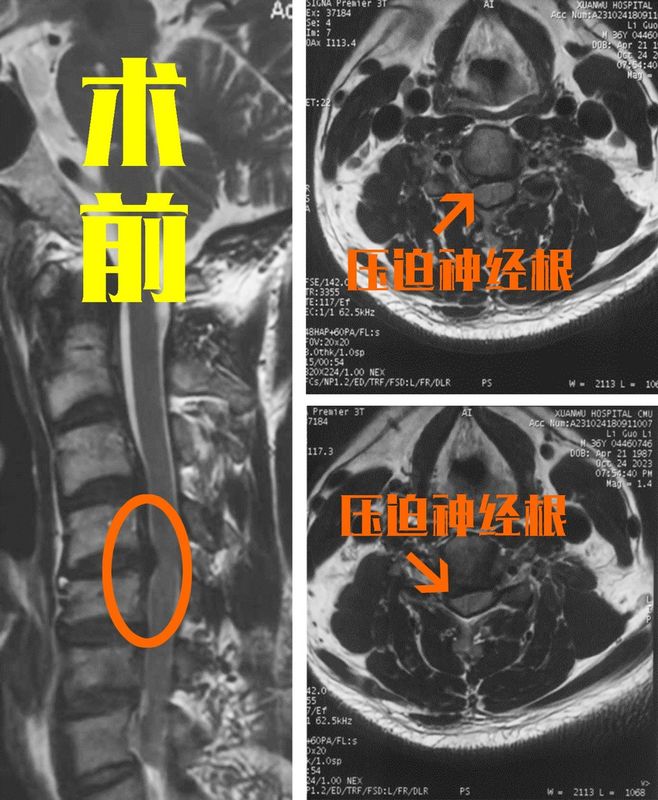

不少頸椎病患者都有過這樣的經(jīng)歷,出現(xiàn)頸部疼痛、胳膊和手部的疼痛麻木后去醫(yī)院檢查,查出了神經(jīng)根型頸椎病。大多情況下,醫(yī)生會建議他們先進(jìn)行保守治療,但過了幾年后,保守效果變差,癥狀反反復(fù)復(fù),還越來越嚴(yán)重,這時醫(yī)生就會讓患者考慮手術(shù)處理了。有些患者就不理解了,是不是得了神經(jīng)根型頸椎病遲早都要手術(shù)?其實(shí)這個問題是許多患者的誤解,并不是說得神經(jīng)根型頸椎病時間久了就一定會進(jìn)入到需要手術(shù)的階段,那到底出現(xiàn)什么情況才會考慮手術(shù)呢?大部分神經(jīng)根型頸椎病患者并不需要手術(shù)!神經(jīng)根型頸椎病算是所有頸椎病類型中最常見的一種,所以這種類型的頸椎病患者非常多。但大家也不用聽見這種病就害怕,因?yàn)榇蟛糠诌@種患者通過保守治療后,癥狀都能得到緩解,而病情得到控制后就不用再考慮手術(shù)了。但大家應(yīng)該明白保守治療并不是從根本上治療神經(jīng)根型頸椎病,不管是吃藥還是牽引、按摩、理療、針灸等都是治標(biāo)不治本,它們要么可以緩解神經(jīng)水腫、炎性反應(yīng),要么可以放松肌肉痙攣,以達(dá)到緩解癥狀的目的。如果患者在日常生活中仍然長期低頭、使用一些不良姿勢、不愛鍛煉等,這些都會讓我們的癥狀反復(fù)。出現(xiàn)什么情況,神經(jīng)根型頸椎病患者將邁入手術(shù)臺?近日,宣武醫(yī)院王作偉主任就收治了一位典型的神經(jīng)根型頸椎病患者?;颊吣行?,36歲,在2年前出現(xiàn)右胳膊、右手的放射性疼痛、麻木,后經(jīng)保守治療后效果較好。但是今年開始,他自己感覺保守治療效果變差,甚至還出現(xiàn)了右上肢無力的情況,最近一段時間癥狀嚴(yán)重影響日常辦公和生活,這才來到了王主任的門診。經(jīng)過詳詢病史、細(xì)致查體和觀察影像學(xué)片子后,發(fā)現(xiàn)這位患者出現(xiàn)頸椎間盤突出并嚴(yán)重壓迫了右側(cè)的神經(jīng)根。而神經(jīng)根如果長時間嚴(yán)重受壓,導(dǎo)致神經(jīng)損傷后會出現(xiàn)不可逆的功能障礙,再加上患者保守效果不好,嚴(yán)重影響生活,王主任還是建議他盡早進(jìn)行手術(shù),給神經(jīng)減壓,而且越早手術(shù)效果越好。術(shù)前影像學(xué)檢查:一般來說,如果神經(jīng)根型患者出現(xiàn)上肢無力、肌肉力量減弱以及手部肌肉萎縮等情況就說明神經(jīng)受壓很嚴(yán)重了;還有患者的癥狀嚴(yán)重影響生活,比如疼得睡不著、天天難受啥也干不了,經(jīng)過正規(guī)保守治療也沒啥效果,這些情況就需要盡快考慮手術(shù)了。手術(shù)后癥狀會快速緩解,但仍需要注意術(shù)后康復(fù)、預(yù)防復(fù)發(fā)!這位患者最后還是選擇了手術(shù)治療,手術(shù)由王主任成功進(jìn)行,切除了突出的椎間盤,給神經(jīng)根進(jìn)行了徹底減壓。手術(shù)后,患者立馬就感到自己的疼痛大大減輕,麻木、無力也得到了明顯緩解。術(shù)后影像學(xué)檢查:當(dāng)然,對和這位患者一樣的神經(jīng)根型頸椎病患者來說,手術(shù)并不意味著治療的結(jié)束,還需要他們做好術(shù)后的康復(fù)工作和頸椎的日常保健,這樣才能鞏固手術(shù)效果,降低術(shù)后復(fù)發(fā)幾率。